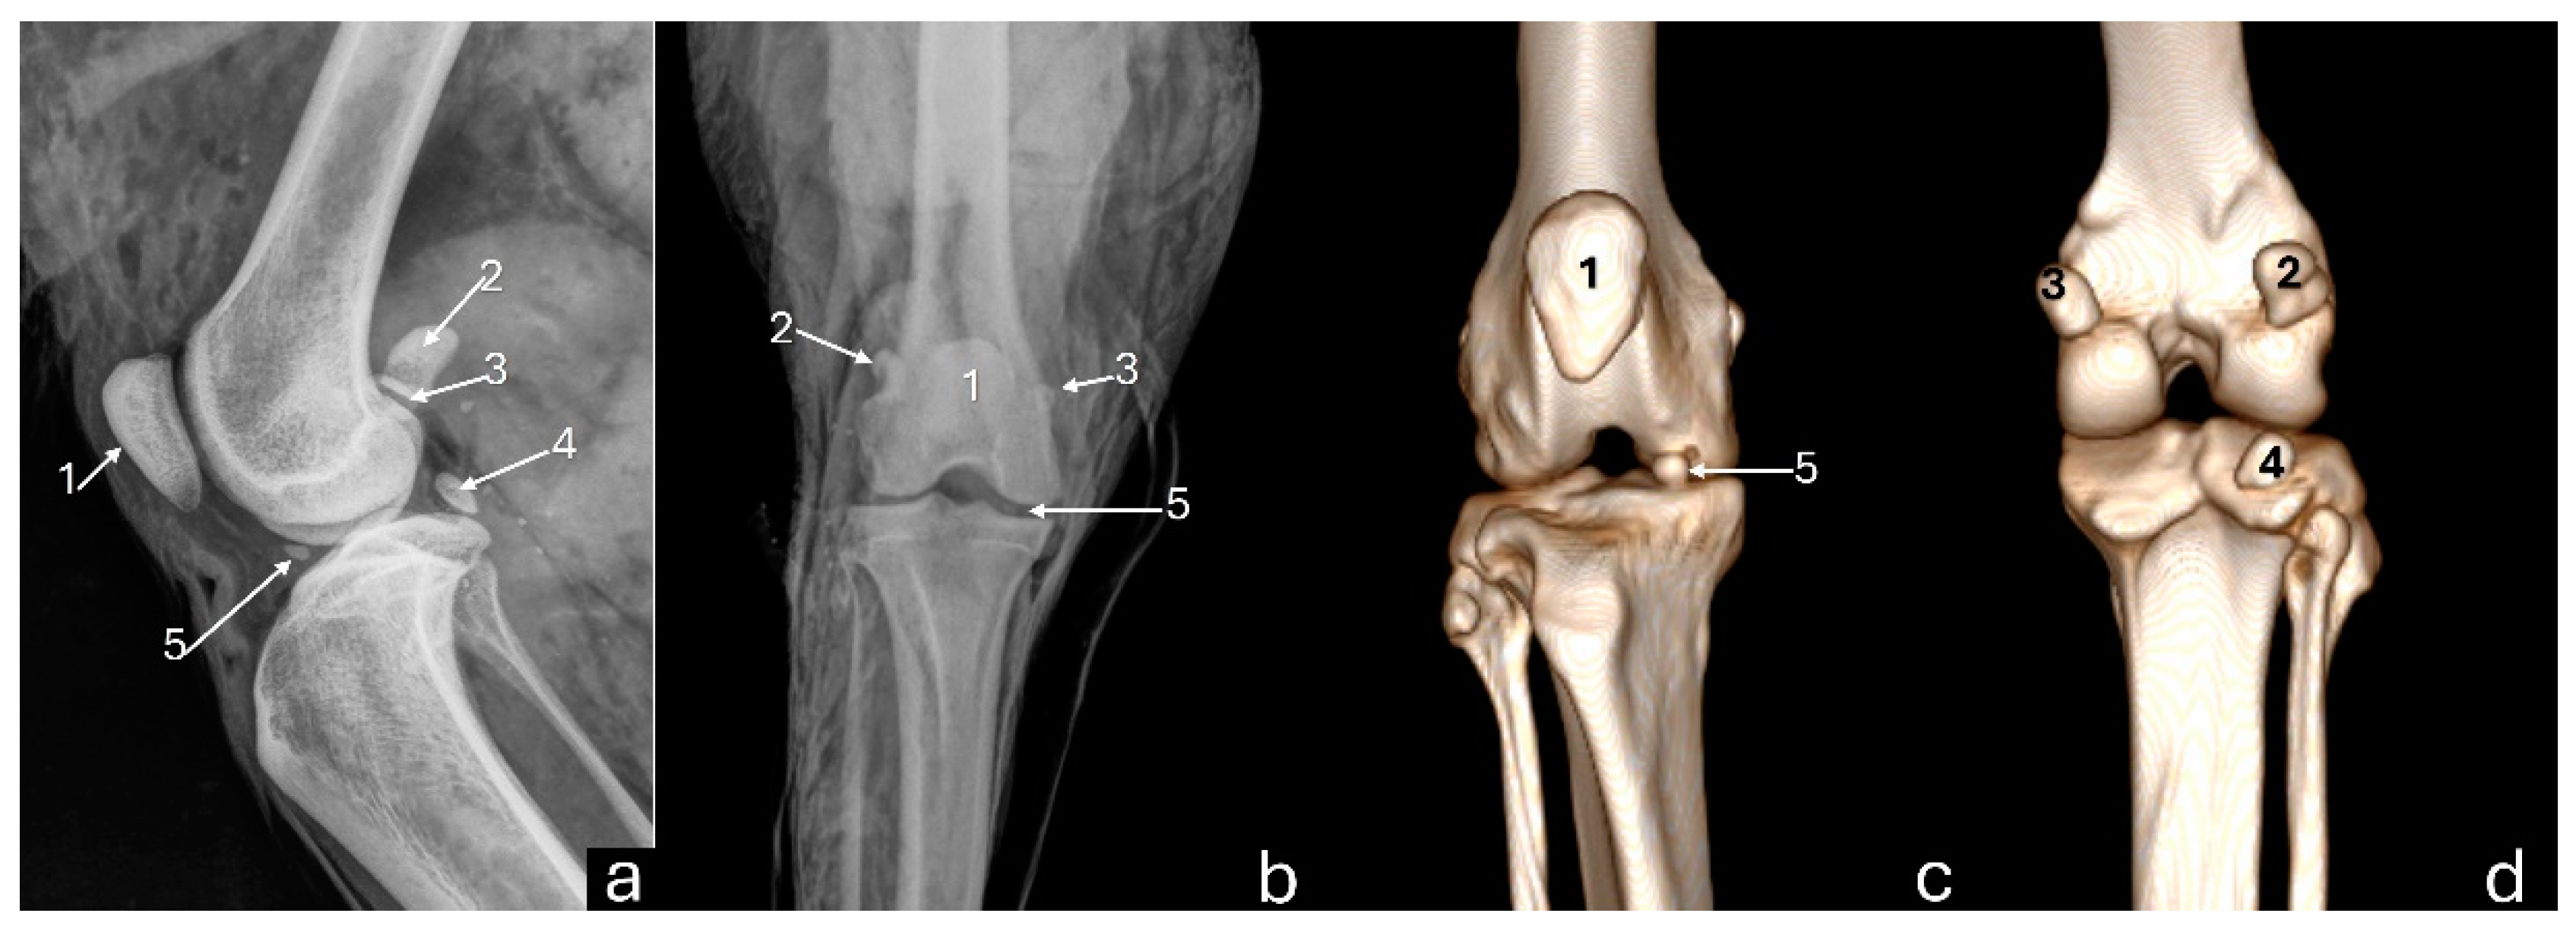

Figure 2. Radiographs in mediolateral (a) and craniocaudal (b) views, and 3D reconstruction computed tomography images in cranial (c) and caudal (d) views of an adult puma stifle joint (Puma concolor). 1 - patella, 2 - lateral fabella, 3 - medial fabella, 4 - popliteal sesamoid, 5 - mineralization of the medial meniscus.

On the mediolateral radiographic view (Figure 2a), the patella had a triangular shape with a wider base than the apex, positioned in the trochlear groove. The femoral condyles had a convex surface without overlap, with the lateral condyle larger than the medial condyle. The articular surface of the tibia had a convex appearance. The fabellae and sesamoid of the popliteal muscle were identified. An intra-articular radiopaque structure consistent with partial meniscus mineralization was observed in the stifles of three adults and one young animal. On the craniocaudal radiographic view (Figure 2b), well-defined and convex femoral condyles on the articular surface were visualized, with the lateral condyle larger than the medial one. The patella was oval and positioned in the trochlear groove. The extensor fossa was identified on the lateral condyle. The surface of the lateral and medial tibial condyles had a slightly convex appearance, with the lateral one being larger. The intercondylar eminence was clearly defined, showing two intercondylar tubercles, with the lateral one larger than the medial one, and a central intercondylar area. The lateral and medial fabellae were visualized as rounded radiopaque structures in the epicondylar region of the lateral and medial condyles, respectively. The lateral fabella was larger than the medial one. The head of the fibula was articulated with the tibia. In the medial compartment of the femorotibial joint, a radiopaque structure was seen, compatible with meniscal mineralization in the same four animals.

The 3D reconstruction of CT images (Figure 2c) revealed, in a cranial view, the patella as a raindrop-shaped structure with a wider base than the apex, positioned in the symmetrical trochlear groove. Meniscal mineralization was identified in the stifles of the same four animals as a hyperdense portion in the medial compartment. The caudal and lateral views displayed the lateral and medial fabellae in the epicondylar region of the lateral and medial condyles, respectively, with the lateral one being larger (Figure 2d). Other bone structures showed similar patterns as seen in radiographic images. Multiplanar and cross-sectional images allowed identification of the patella, infrapatellar fat, cranial cruciate ligament (from the caudal portion of the femur to the cranial area of the tibia), caudal cruciate ligament (from the cranial aspect of the femur to the popliteal margin of the tibia) and meniscofemoral ligament (Figure 3). The menisci were more difficult to identify, but those with partial mineralization were easily visualized (Figure 4). The fabellae and sesamoid of the popliteal were also identified; all had a thin cortical layer.

Figure 5 displays radiographs and CT images of the stifle joint of a young puma where no meniscal mineralization is detected.